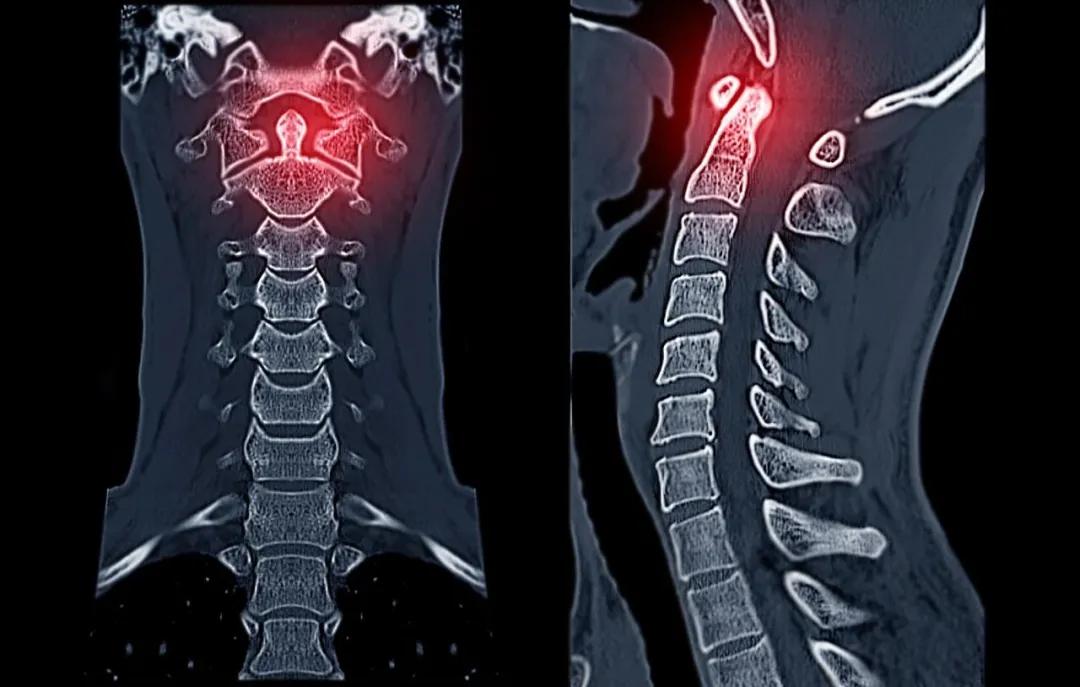

强直性脊柱炎(AS)是一种脊柱的慢性进行性炎症,属于自身免疫性疾病的一种,主要累及脊柱关节、骶髂关节及其邻近的软组织,如肌腱和韧带。有较强的遗传因素。它主要侵犯骶髂关节和脊柱。早期多表现为脊柱及关节疼痛,晚期由于行动受限,多发生肌肉萎缩及脊柱关节畸形,导致患者残疾并严重影响患者劳动能力。

除了病变关节间歇性、反复性的疼痛、晨僵表现外,还可能出现脊柱活动受限、姿势异常,甚至引起炎症性肠病、急性前葡萄膜炎、椎体脆性骨折等,严重影响患者的生活质量。